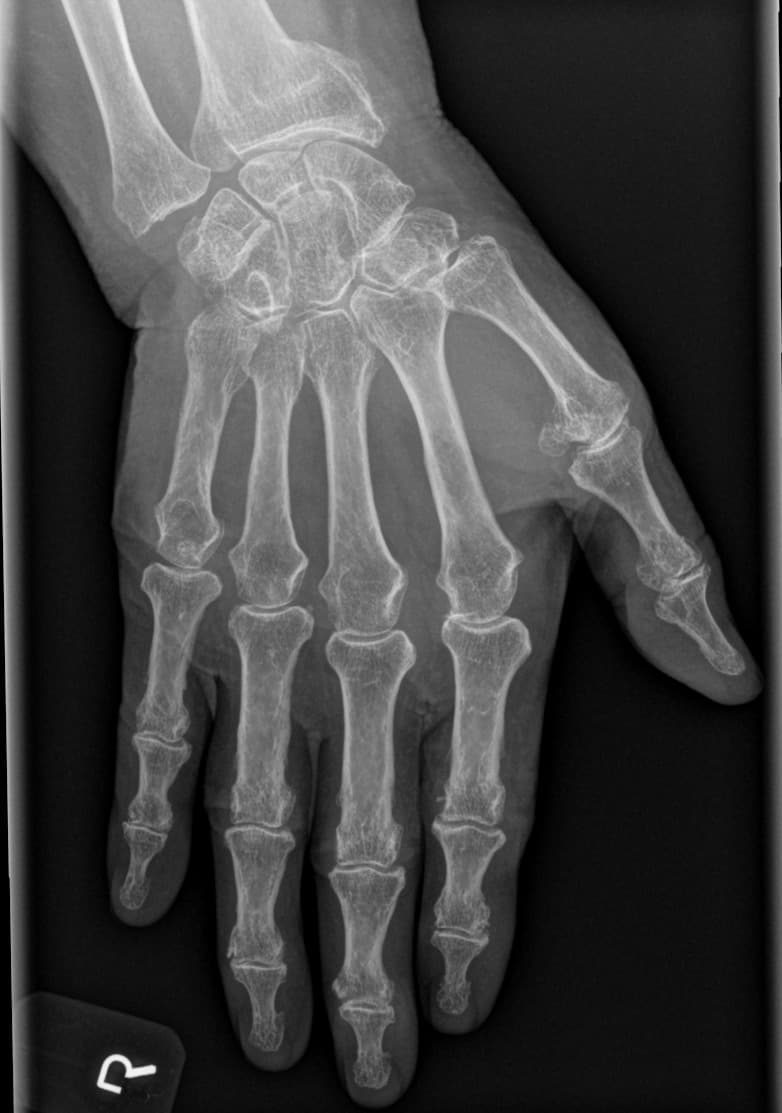

En kort ramme til sammenligning af aktuelle og tidligere røntgenundersøgelser i second-opinion vurdering.

Læs artikel